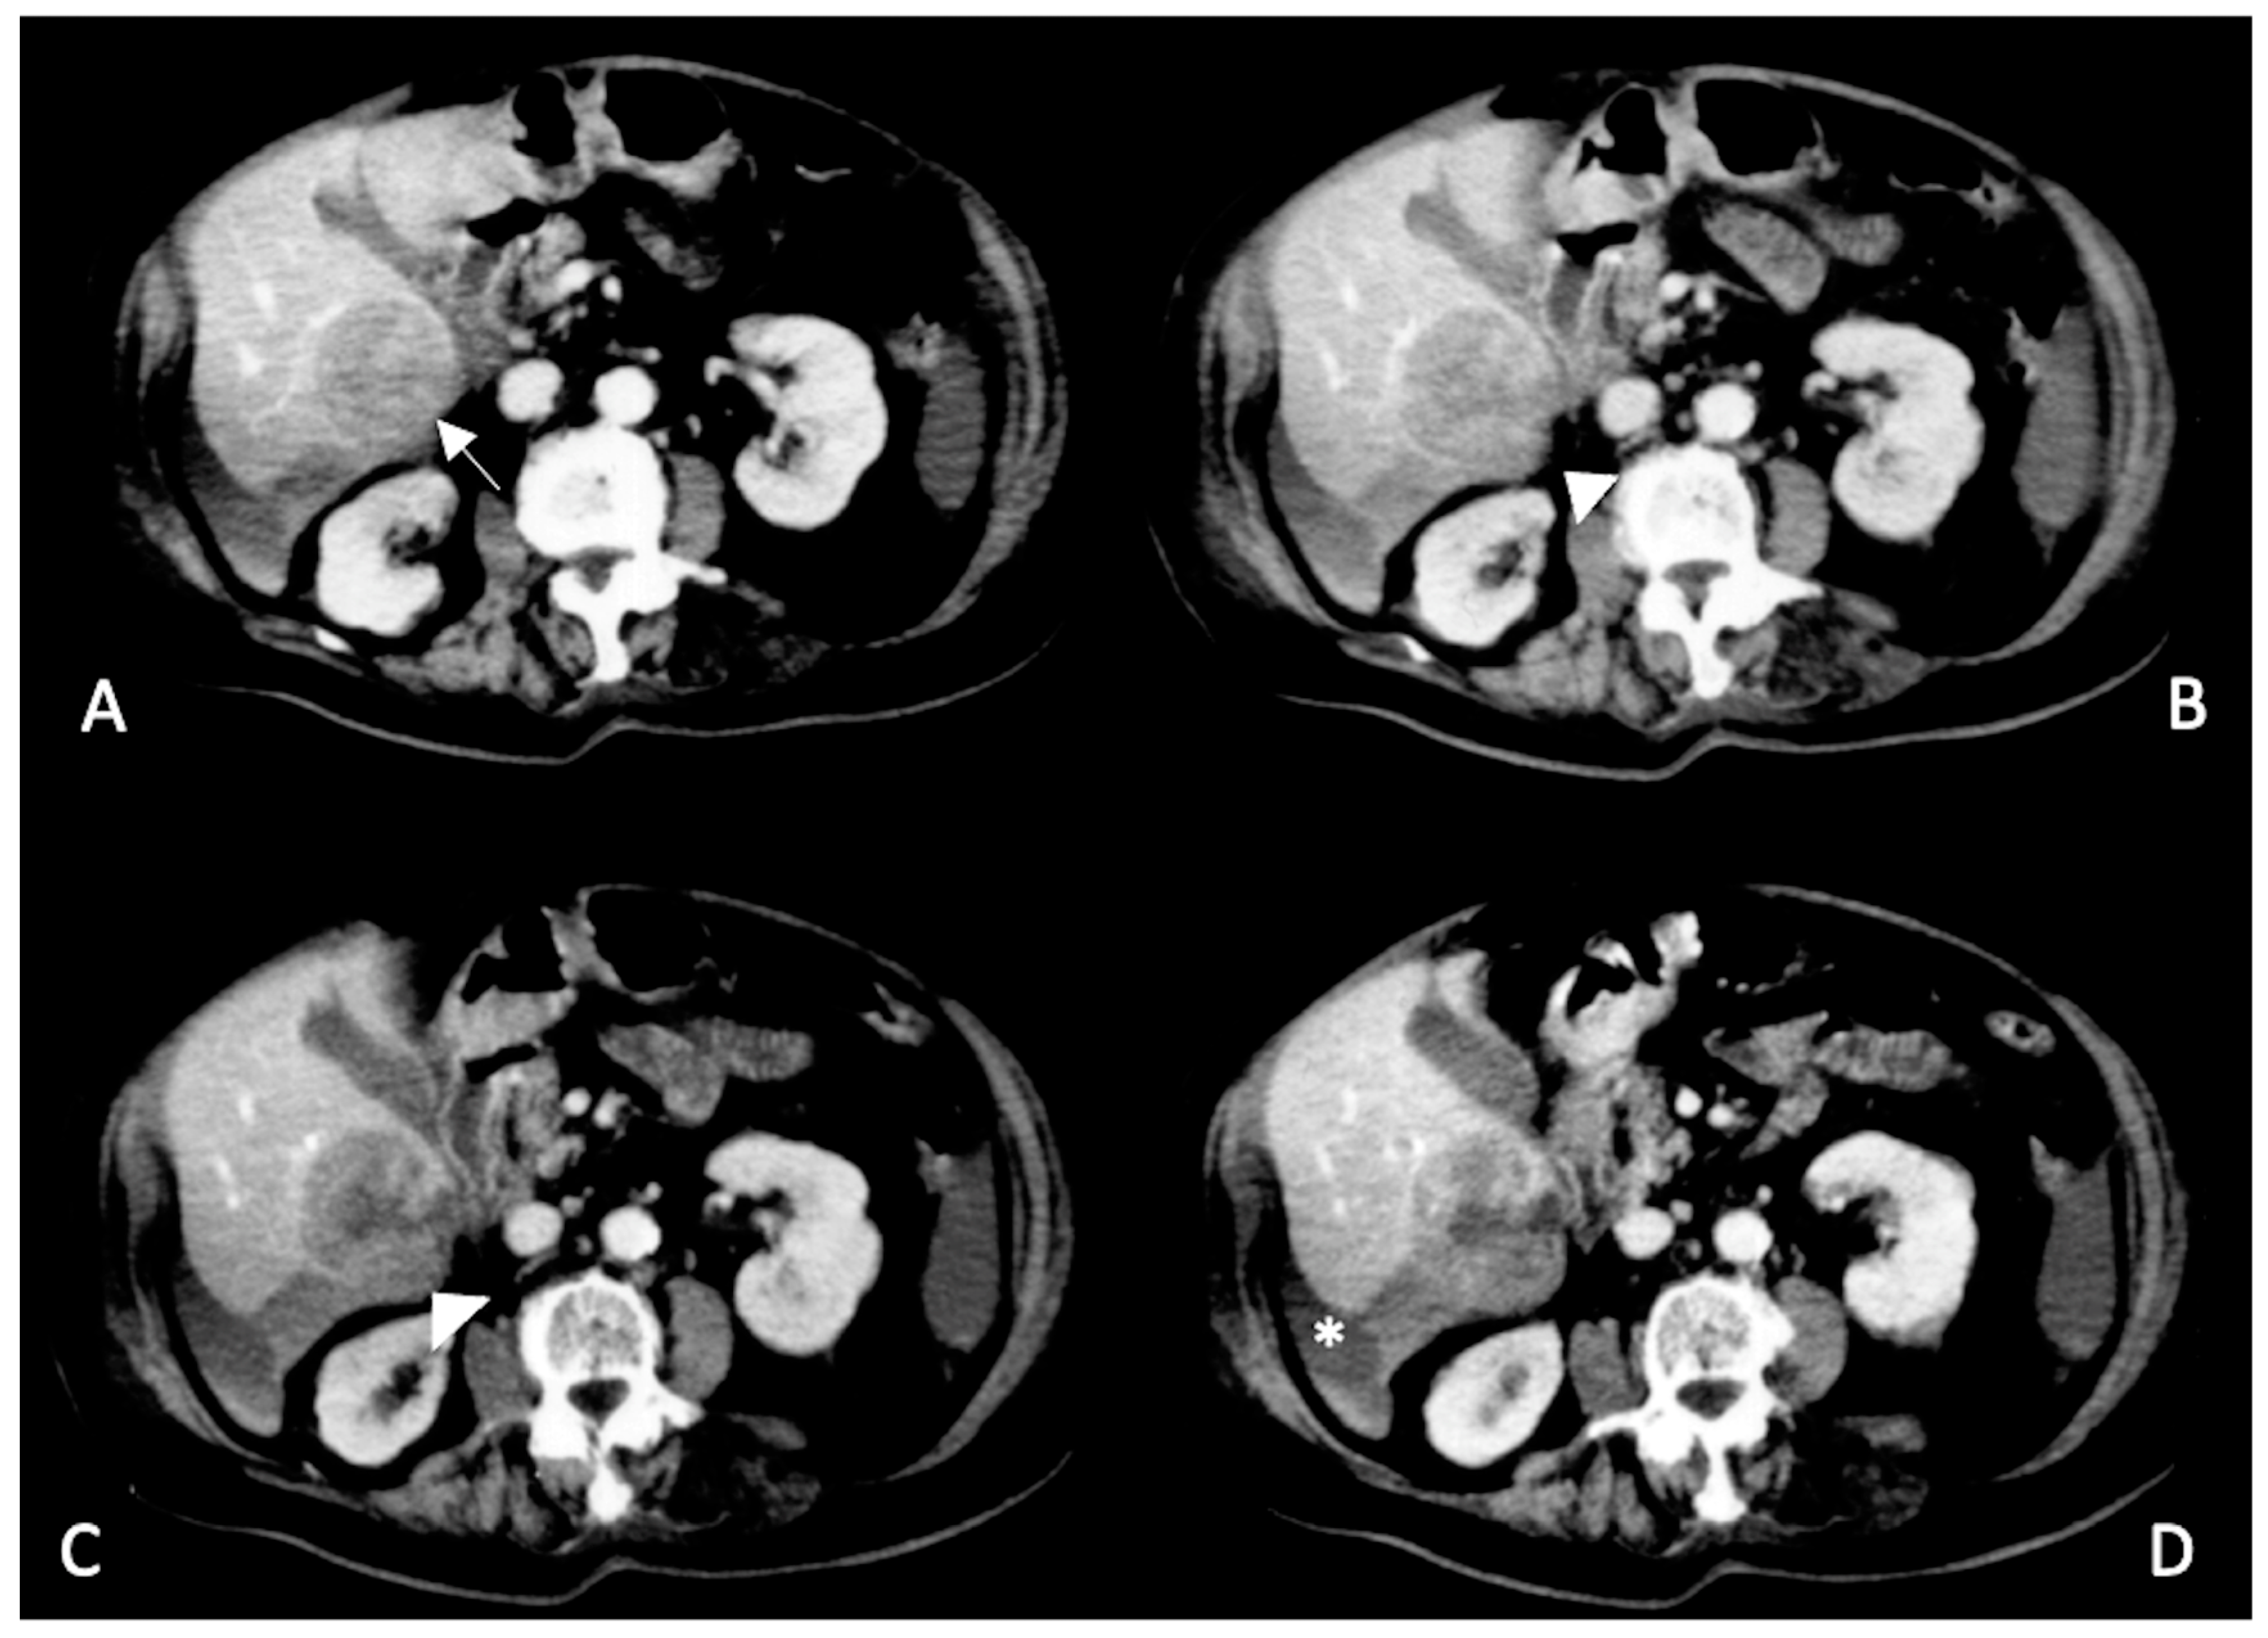

2. CT Findings

2.2. Spontaneously Ruptured HCC (SRHCC)